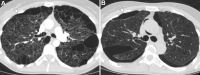

As lung transplantation has become the most effective definitive treatment option for end-stage chronic respiratory diseases, yearly rates of this surgery have been steadily increasing. Despite improvement in surgical techniques and medical management of transplant recipients, complications from lung transplantation are a major cause of morbidity and mortality. Some of these complications can be classified on the basis of the time they typically occur after lung transplantation, while others may occur at any time. Imaging studies, in conjunction with clinical and laboratory evaluation, are key components in diagnosing and monitoring these conditions. Therefore, radiologists play a critical role in recognizing and communicating findings suggestive of lung transplantation complications. A description of imaging features of the most common lung transplantation complications, including surgical, medical, immunologic, and infectious complications, as well as an update on their management, will be reviewed here. Keywords: Pulmonary, Thorax, Surgery, Transplantation Supplemental material is available for this article. © RSNA, 2021.